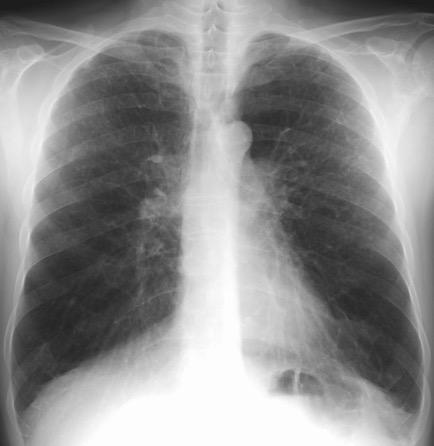

1. < Volumen pulmonar

Fibrosis intersticial

Asbestosis

Sarcoidosis

Fibrosis pulmonar

Neumonitis de hipersensibilidad

Sind. antisintetasa

2.Atelectasia bilateral

3. Enf. neuromuscular

Rajan SK et al. Progressive pulmonary fibrosis: an expert groupconsensus statement. Eur Respir J 2023;

Nason LK. Imaging of the diaphragm: anatomy and function. Radiographics 2012